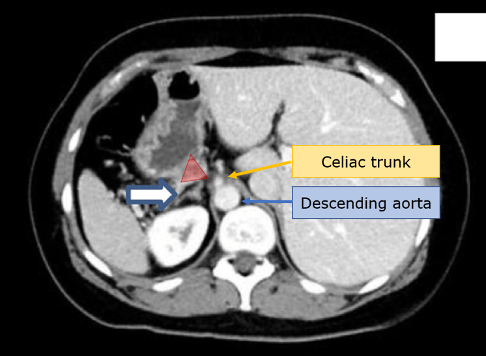

ข้อดีที่สำคัญอย่างหนึ่งของการทำ EUS-B ในการกำหนดระยะของมะเร็งปอดร่วมกับ EBUS คือการเข้าถึงตำแหน่งของต่อมหมวกไตซ้าย (left adrenal gland) ได้ เนื่องจากต่อมหมวกไตเป็นตำแหน่งที่พบการแพร่กระจายจากมะเร็งปอดได้ถึงร้อยละ 1.3817 จึงเป็นตำแหน่งที่ควรมองหาทุกครั้งเมื่อต้องการตรวจหาระยะของมะเร็ง โดยตำแหน่งที่จะสามารถตรวจพบต่อมหมวกไตซ้ายได้อยู่ที่บริเวณกระเพาะอาหาร (gastric approach) เนื่องจากเป็นตำแหน่งที่ต่อมหมวกไตซ้ายเข้ามาชิดกับกระเพาะอาหารบริเวณรอยต่อกับหลอดอาหารพอดีดังรูปที่ 1. โดยต่อมหมวกไตซ้ายปกติจะเห็นภาพจากอัลตราซาวด์เป็น “Seagull configuration” hypo-echoic area จนถึงปัจจุบันได้มีการศึกษาที่แสดงถึงความสำเร็จและความปลอดภัยในการทำ EUS-B FNA ที่ตำแหน่งต่อมหมวกไตซ้าย โดยพบว่าสามารถแสดงให้เห็นต่อมหมวกไตซ้ายจาก EUS-B ได้สำเร็จถึงร้อยละ 85-8718–19 และสามารถทำ FNA ได้สำเร็จถึงร้อยละ 87 นอกจากนี้มีการศึกษาไปข้างหน้า (Prospective trial) ในเรื่องนี้ขนาดใหญ่ (prospective trial) ในปี 2019 ทำการศึกษาผู้ป่วยที่สงสัยมะเร็งในช่องอกและมีต่อมน้ำเหลืองในช่องอกโต 313 ราย ในประเทศเยอรมันโดยใช้ EUS-B ค้นหาและเก็บตัวอย่างต่อมหมวกไตซ้าย พบว่าแพทย์ที่มีความชำนาญด้านการทำ EBUS แต่ยังไม่เคยมีประสบการณ์ทำ EUS มาก่อน 4 ท่านสามารถค้นหาต่อมหมวกไตซ้ายได้เฉลี่ยร้อยละ 87.5 ของผู้ป่วยทั้งหมด โดยเพิ่มขึ้นตามระยะเวลาที่ฝึกฝนและจำนวนผู้ป่วยที่ทำไป ในส่วนของการเก็บตัวอย่างจาก EUS-B FNA มีความไว ความจำเพาะ และการทำนายผลลบ (NPV) อยู่ที่ร้อยละ 75, 100, และ 95.7 ตามลำดับ ทั้งนี้ไม่พบภาวะแทรกซ้อนที่เกิดจากการทำ EUS-B FNA เลย ดังนั้นการเก็บตัวอย่างต่อมหมวกไตซ้ายด้วย EUS-B จึงได้รับการสนับสนุนให้ทำร่วมกับหัตถการอื่นๆในการหาระยะของมะเร็งปอดด้วย

รูปที่ 1. แสดง CT scan (ภาพถูกกลับข้างซ้าย-ขวาเพื่อง่ายต่อความเข้าใจในการส่องกล้อง) ของตำแหน่งต่อมหมวกไตซ้ายปกติ ที่ปลายศรชี้ โดยแถบสี่เหลี่ยมสีแดงคือทิศของอัลตราซาวด์ที่มาจากกระเพาะมายังต่อมหมวกไต